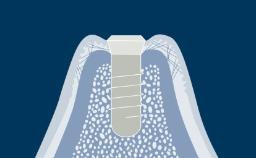

- describe common pathologic conditions affecting the soft tissues

- describe common pathologic conditions affecting the maxilla and mandible

- discuss how these conditions may impact on implant treatment or continuing care